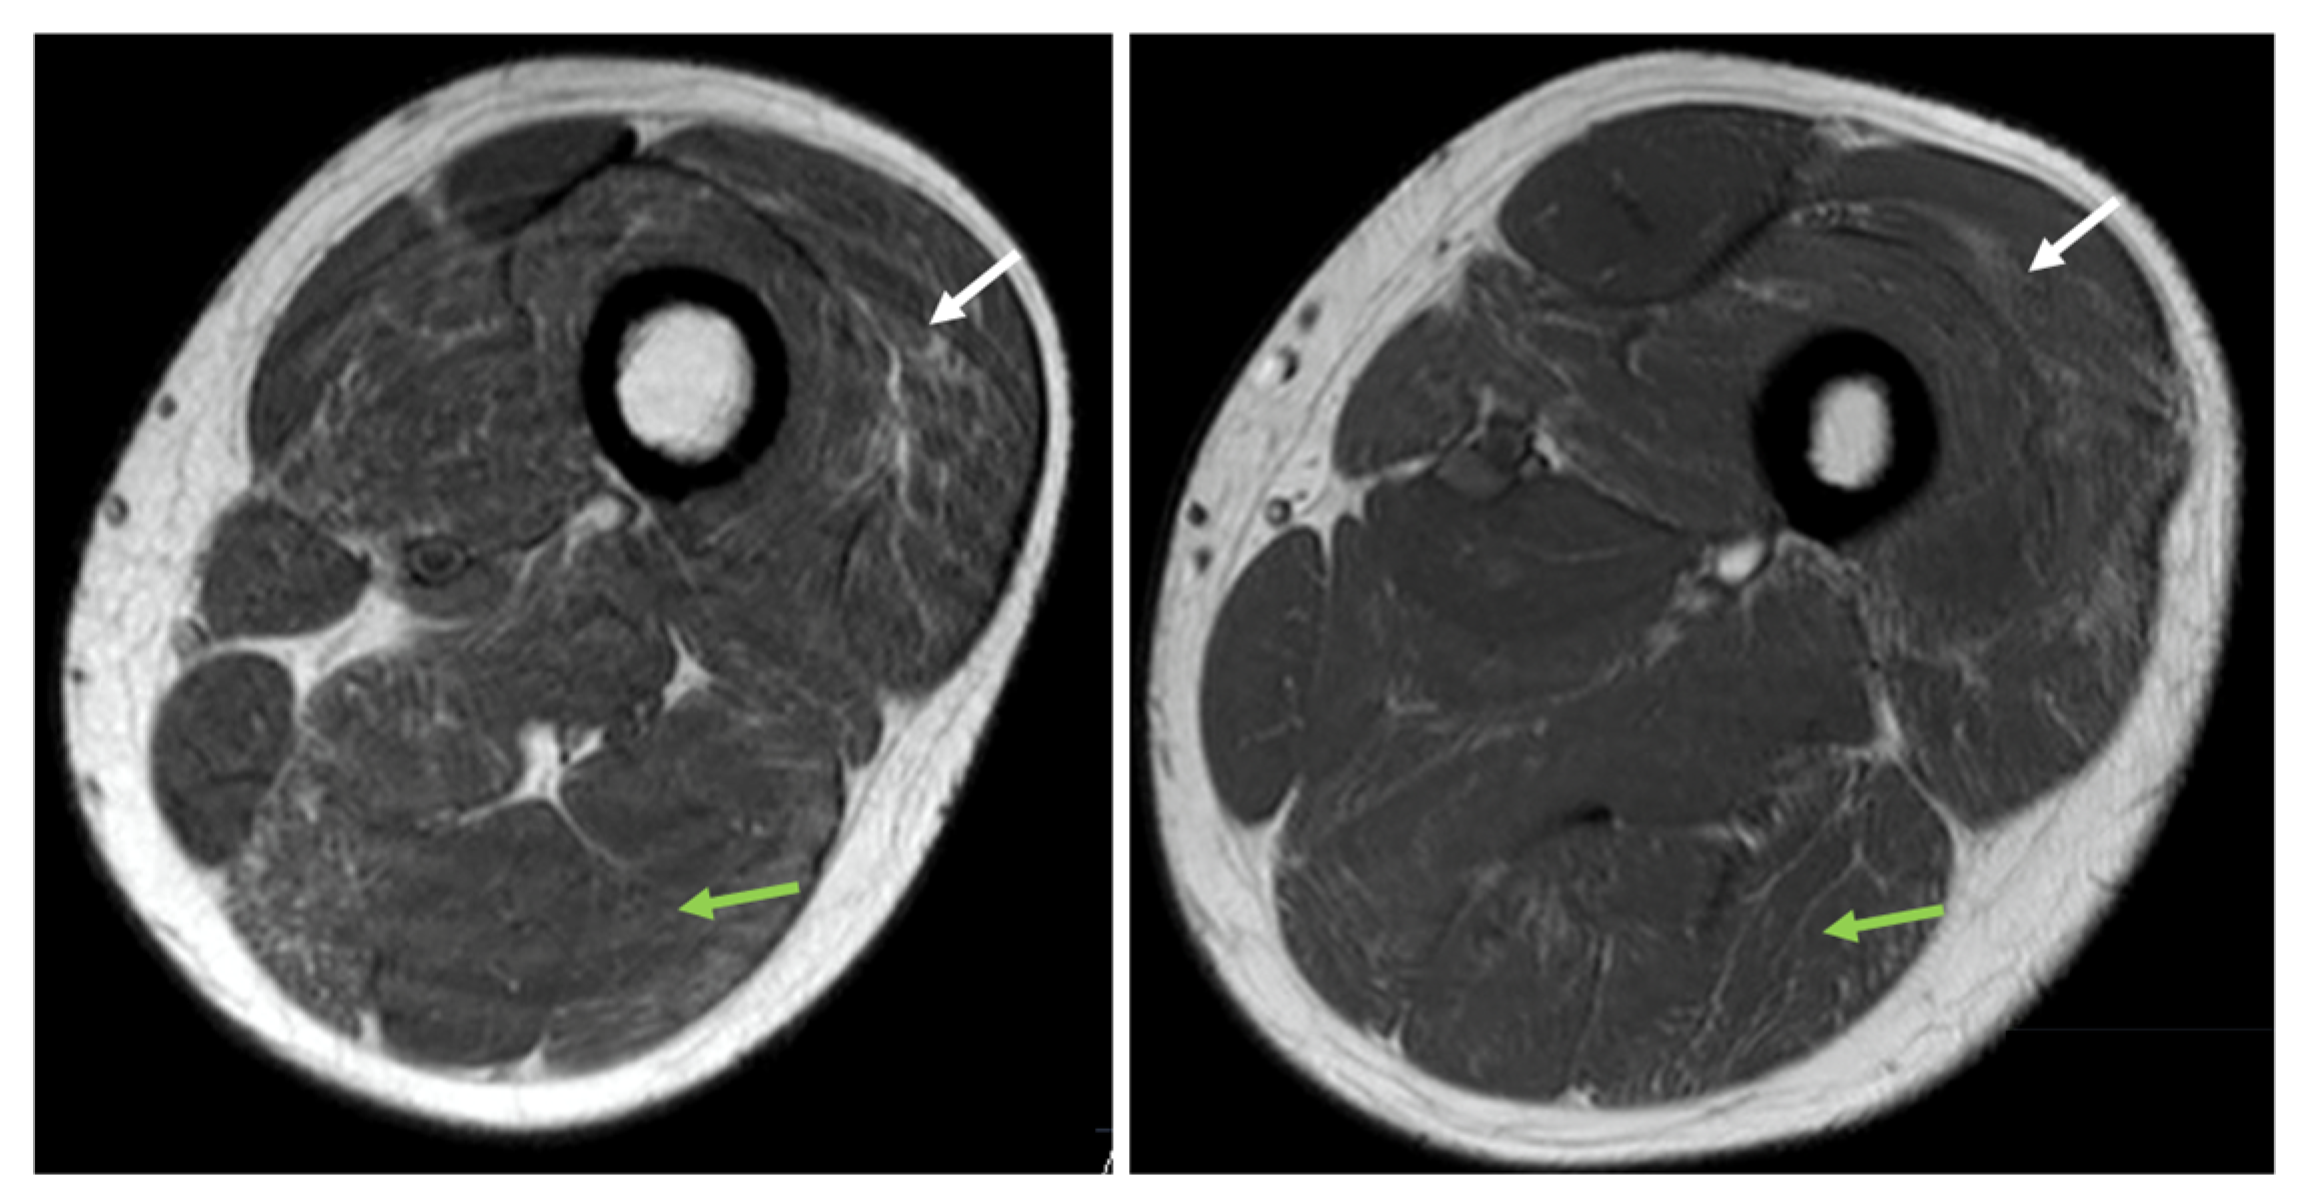

2.1. Case Series Report